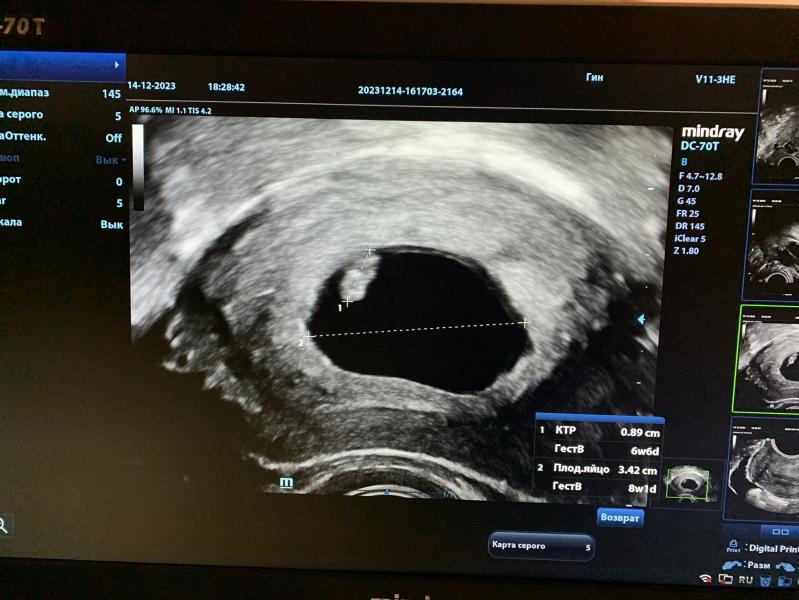

Всем привет👋🏼 Сегодня мы впервые услышали сердечко❤️ И меня поставили на учет🙏🏻 По месячным срок 8,2нед, по узи поставили 7 недель.

Сказали, что все отлично. В конце сделали пометку о том, что есть гематома на шейке, внимание особо не акцентировали, ни узист, ни врач. Сказали, что абсолютно не страшно и не опасно, очень на это надеюсь🙂